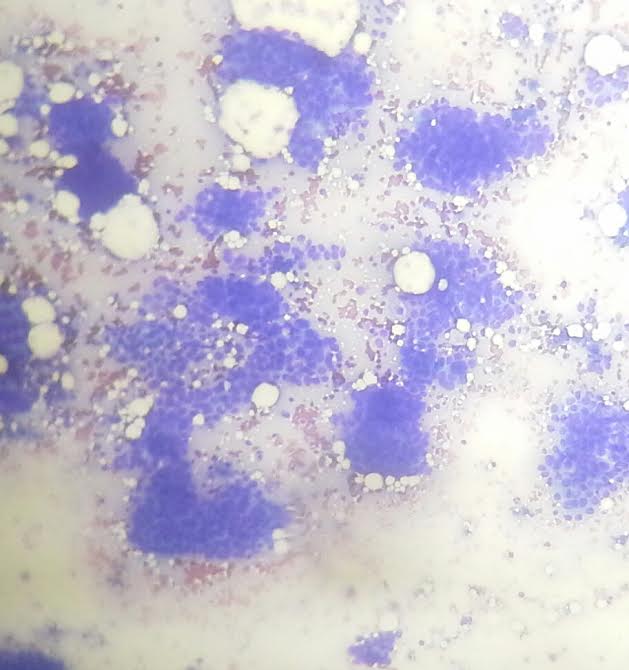

Cytology description

- Can use cellular pleomorphism, nuclear size, nuclear margin, nucleoli, lack of naked nuclei, cellular dyscohesion and mitoses in addition to necrosis to assess cytologic tumor grade, which correlates with histologic grade (Diagn Cytopathol 2003;29:185)

Cytology images